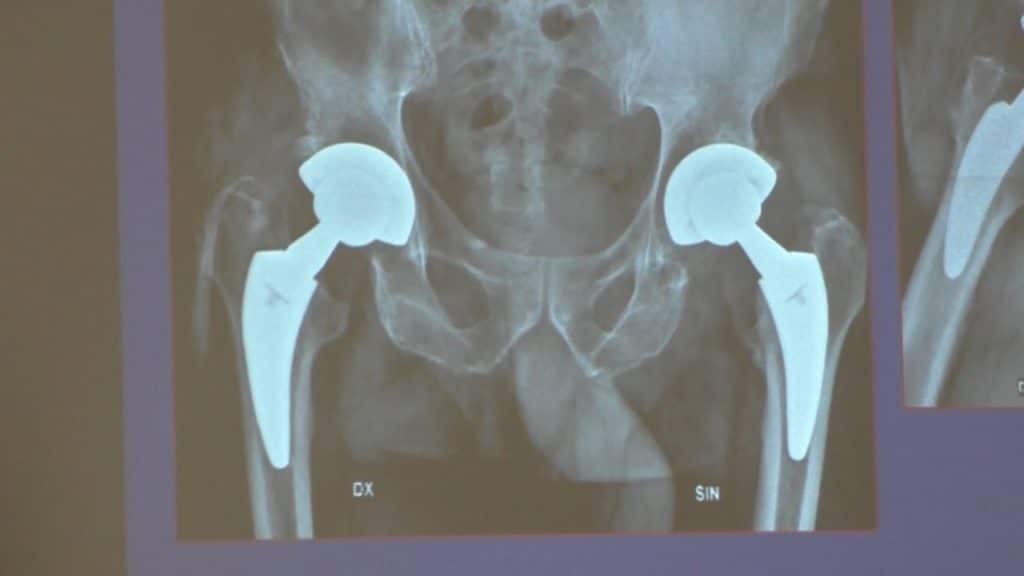

La tecnica SuperPATH consente l’innesto di protesi con una mobilità quasi identica a quella originale e dimezza i tempi di recupero. Merlo: “Pressoché azzerati gli effetti collaterali”